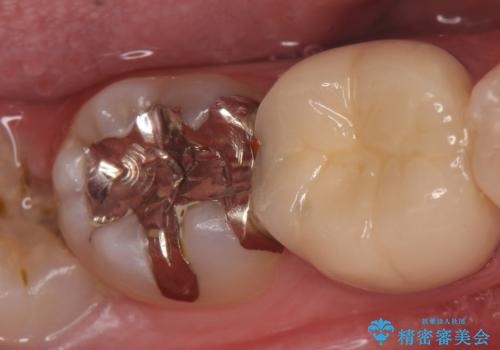

- 右下7の銀歯を白くしたいといらっしゃった方の症例です。

銀歯及び虫歯を除去後、セラミックインレーで修復を行いました。